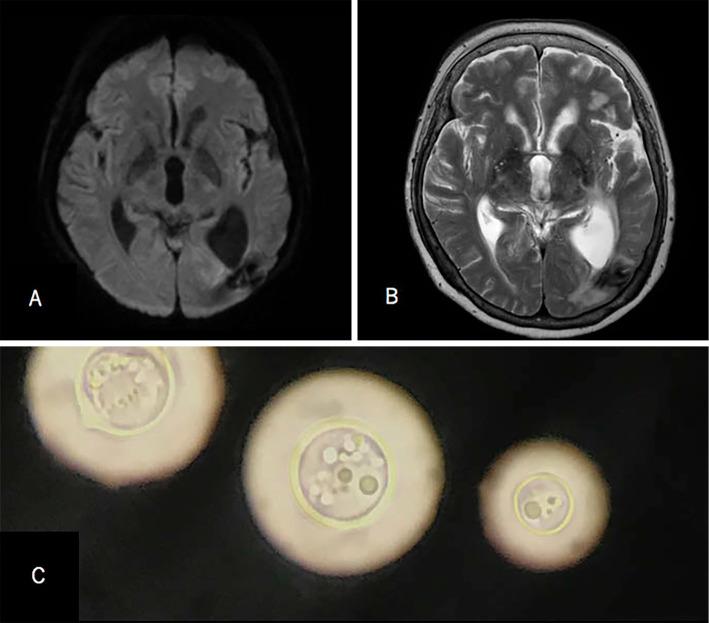

We report a case of disseminated cryptococcosis in a patient with multiple myeloma (MM) during treatment with daratumumab, lenalidomide, and dexamethasone (DRd). A 62-year-old woman, who was diagnosed with IgGλ type MM, was treated with three cycles of bortezomib and dexamethasone and subsequently treated with three cycles of DRd before admission. She reached a stringent complete response and presented with lethargy and seizure. Laboratory findings revealed severe CD4 lymphopenia, and Cryptococcus neoformans was detected in her cerebrospinal fluid and blood culture. The risk of developing an opportunistic infection should be considered in patients treated with daratumumab.

我们报告了1例在使用达雷妥尤单抗、来那度胺和地塞米松(DRd)治疗多发性骨髓瘤(MM)期间发生播散性隐球菌病的病例。一名62岁女性,被诊断为IgGλ型MM,在入院前接受了3个周期的硼替佐米和地塞米松治疗,随后接受了3个周期的DRd治疗。她达到了严格完全缓解,并出现嗜睡和癫痫发作。实验室检查结果显示严重的CD4淋巴细胞减少,脑脊液和血培养中检测到新型隐球菌。接受达雷妥尤单抗治疗的患者应考虑发生机会性感染的风险。